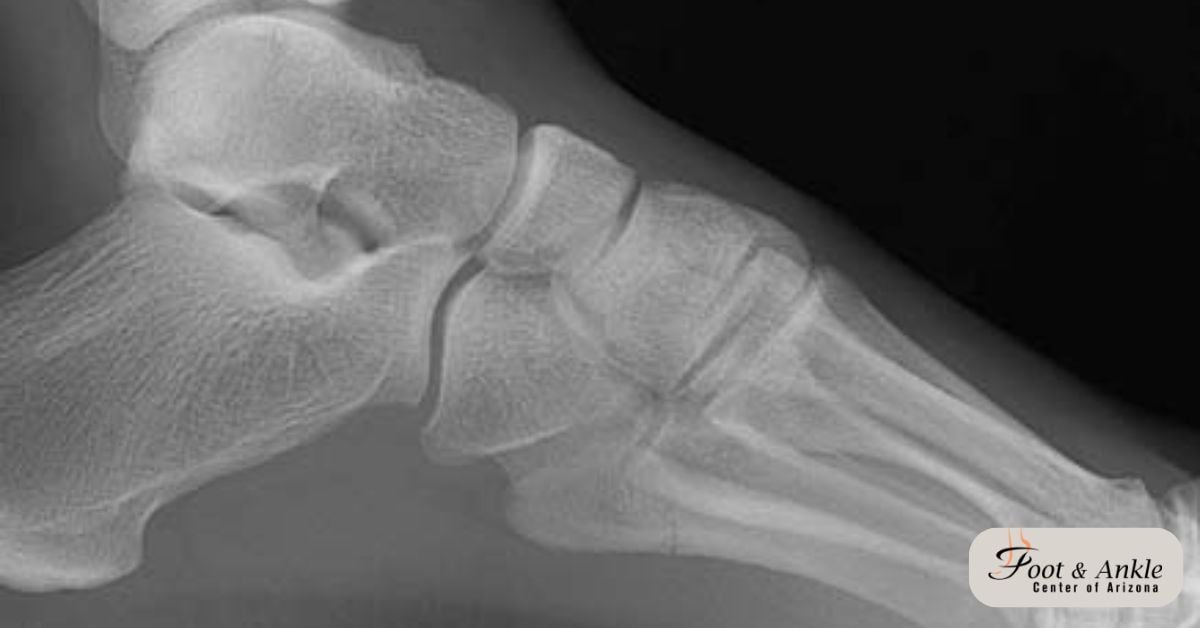

Foot Fractures: A Comprehensive Guide to Treating Your Injury

What is a Metatarsal Fracture?

How long does it take for a Metatarsal Fracture to Heal?

Toe and Metatarsal Fractures (Broken Toes)